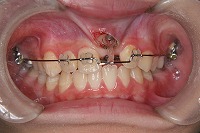

反対咬合と前歯が生えてこない事を主訴に来院された、10歳4か月の男の子です。診断「下顎骨の過成長による骨格性反対咬合で上顎正中の左方偏位と埋伏歯を伴う」1期治療で反対咬合の解消と埋まっていた前歯を牽引しました。